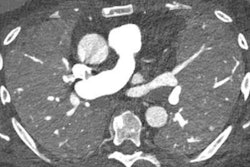

Photon-counting CT enhances image quality for coronary CT angiography exams while also reducing contrast use by up to 40%, Swiss researchers have stated. The technology's higher contrast-to-noise ratio properties are of particular note, they said.

"Increased image quality of photon-counting CT (PCCT) can be used for considerable contrast media volume reduction while still maintaining a diagnostic image quality of CCTA," the team wrote.

"Our study demonstrates the possibility to reduce the volume of contrast media for CCTA by 40% while maintaining a diagnostic image quality ... [by] exploiting the lower noise and higher contrast-to-noise ratio properties of low-energy-level VMI reconstructions with [PCCT]," the team wrote.